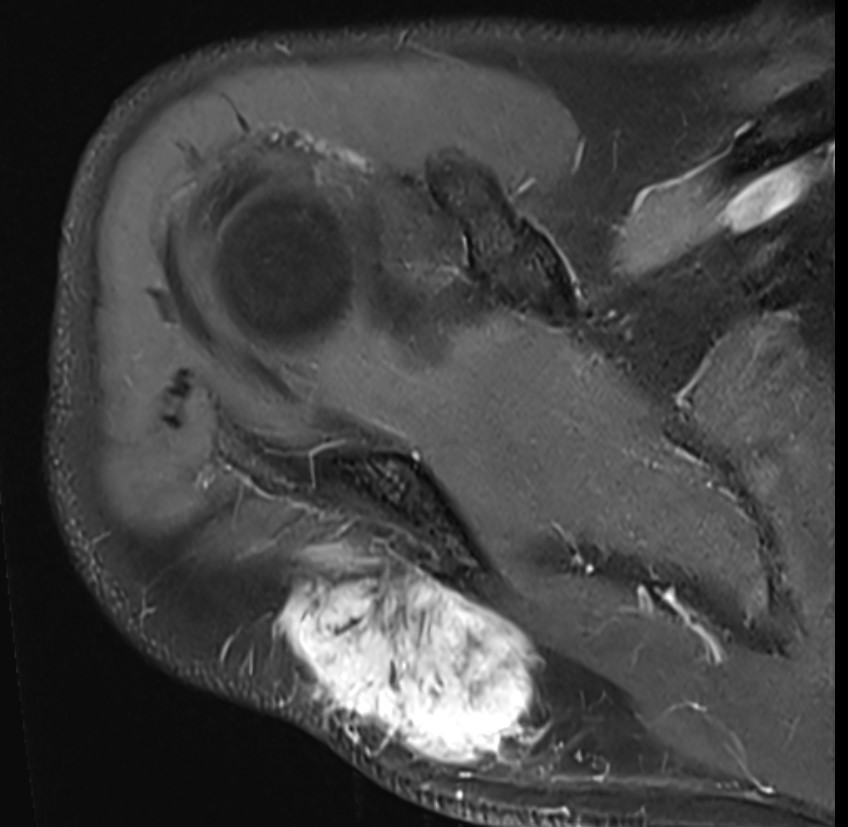

MRI

Soft tissue mass